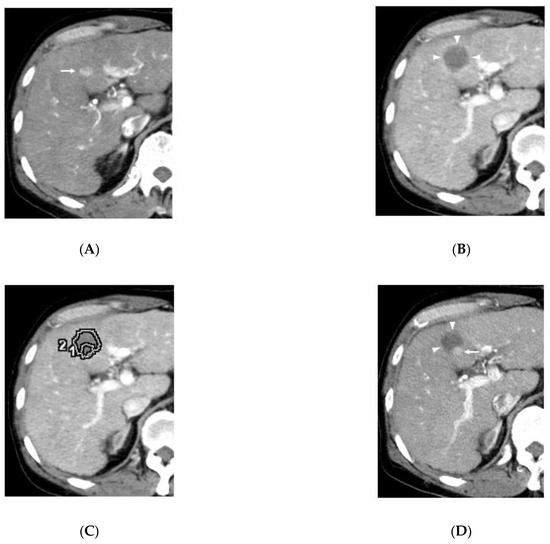

2.2. Three-Dimensional Assessment of Ablative Margins Using Overlay Fused CT/MRI Imaging